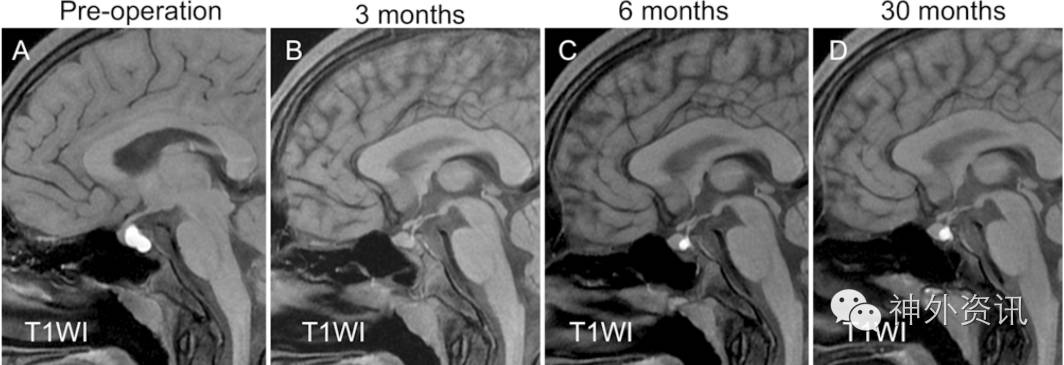

图1. 1例慢性头痛起病的15岁男性患者MRI图像:A.术前MRI-T1显示高信号囊肿;B.术后3个月囊肿消失;C.术后6个月囊肿复发;D.术后30个月囊肿较前扩大。